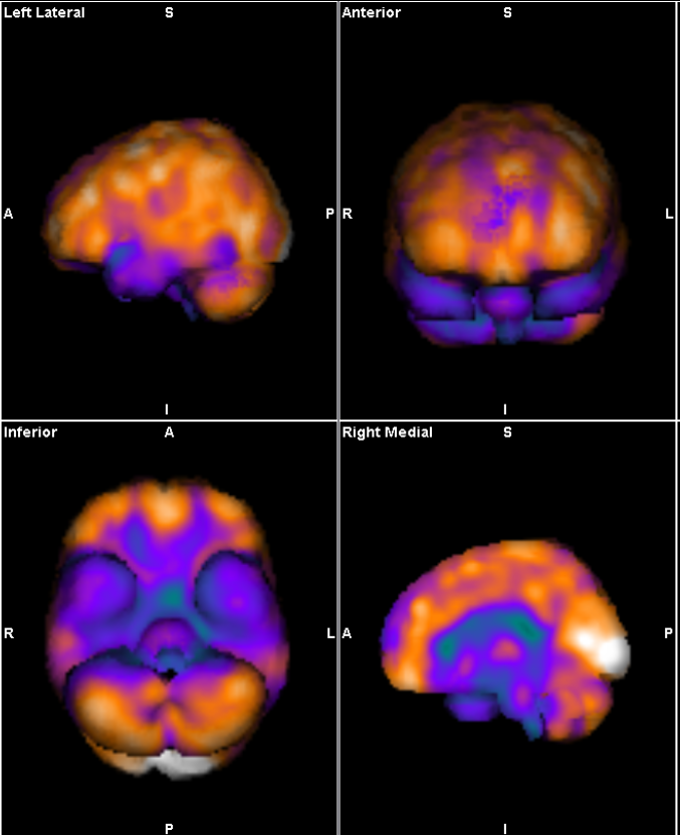

עם ההתפתחות בהדמיות המוח המדגימות תפקוד, ולא רק מבנה, ניתן כיום לזהות הפרעה תפקודית במוחם של הסובלים מהתסמונת הפוסט טראומטית. הדמיות כגון functional MRI ומיפויי מוח מדגימות ירידה בתפקוד של אזורים בקדמת המוח ושל ההיפוקמפוס הנמצאים בהלימה עם ההפרעה בויסות התגובה הרגשית לתזכורות האירועים. הדגמה של הפרעות אלה בהדמיה קשורה בשיעור תגובה נמוך לקשת הטיפולים הפסיכולוגים והפסיכיאטרים המקובלים כיום

בהדמיה תפקודית של רקמת המוח אזורים תפקודיים מודגמים בצבעים בהירים ואילו אזורים בעלי תפקוד נמוך מודגמים בצבעים קרים. בהדמיה זו מודגמת תת פעילות של קדמת המוח (PFC) ושל אזורים טמפורליים בתמונה המאפיינת מטופלים עם PTSD.

Functional MRI המדגים פעילות מוחית בעת ביצוע מטלה לפני ואחרי טיפול בתא לחץ.